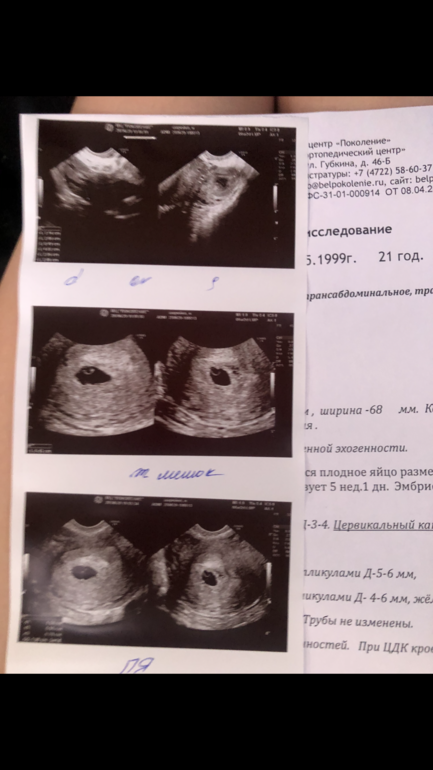

У меня на сроке 4 недели и 4 или 5 дней нашли уже плодное яйцо на узи, задержка была 4 или 5 дней, узи уже должно сказать что-то, если тем более внематочная не дай бог, то будет видно, всегда делают узи чтобы исключить ее, меня для этого и отправляли ) я даже узи вам покажу, 5 недель и 1 день пишут, но по факту зачатие было позже, потом врач сказал что на 3 дня меньше срок

Если подозревают внематочную бегите на узи, вам узист скажет, мне на 5 неделе уже плодное яйцо нашли, если срок +- такой хороший узист вам скажет что и как, если переживаете )